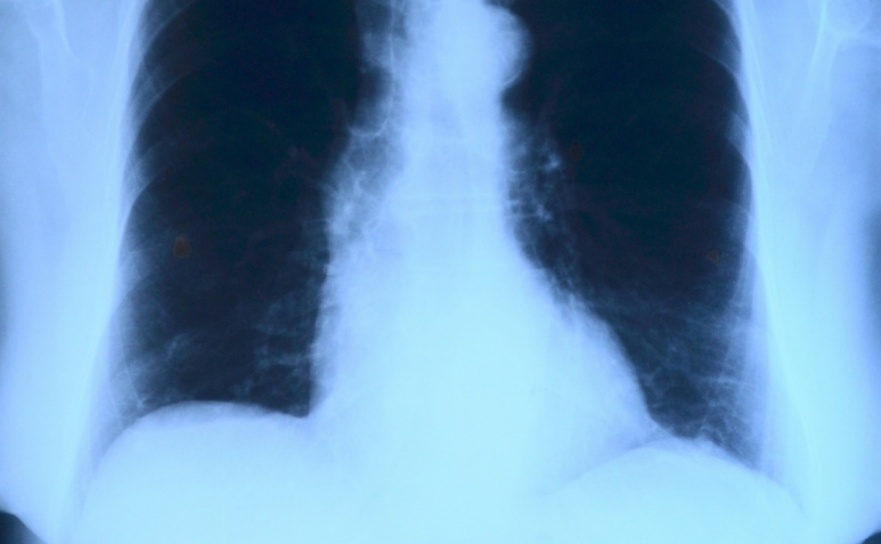

Oddział, obsługujący dziś sporo pacjentów, m.in. z powodu epidemii COViD-19, ma nowego kierownika. To lek. med. Maciej Nowak – specjalista chorób wewnętrznych, specjalista chorób płuc. Dotychczasowy kierownik przeszedł na emeryturę. Luka kadrowa wymusiła zawieszenie na trzy miesiące działalności poradni pulmonologicznej. Jak poinformował na ostatniej konferencji prasowej dyrektor szpitala Ryszard Rudnik, w pierwszej kolejności najważniejsze jest ustabilizowanie sytuacji kadrowej na oddziale, a następnie przywrócenie działalności poradni. Ma to nastąpić około kwietnia. Niewykluczone, że dotychczasowy kierownik będzie nadal współpracował ze szpitalem.